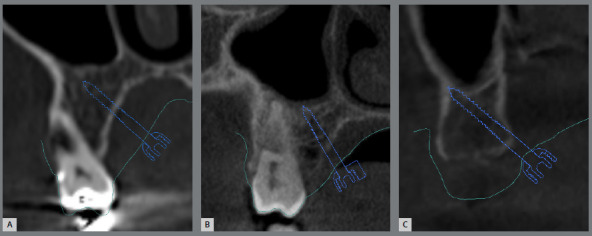

Objective: This cross-sectional study evaluated the bone thickness on mini-implants insertion site, the factors that influence the digital planning of MARPE appliance (miniscrew-assisted rapid palatal expansion), and its different designs.

Methods: A total of 135 plannings were assessed regarding the size of the expander screw used, the positioning and the type of the mini-implant rings, and their location in relation to the teeth. Bone thickness measurements were assessed in the region of the mini-implants' trajectory. Differences between the sexes was verified using the ANOVA test (5% significance).

Results: 73 cases were planned with 4 mini-implants and 62 cases, with 6 mini-implants. In 90% of cases, teeth #16 and #26 were used as supports, and the most used expander screw was 13mm (64.1% of cases). The anterior mini-implants of conventional MARPE showed more pronounced insertion in bone in males (5.9 ± 2mm; p= 0.025). The extra mini-implants (anterior region) were inserted with greater bone thickness in males (11.1 ± 2.3mm) compared to females (9.9 ± 1.8mm; p=0.041). A greater bone thickness was observed in males (10.1 ± 2.1 mm) when using mini-implants in the paramedian region.

Conclusion: Additional rings allow more pronounced bone insertion. Male patients had greater bone thickness, which may be related to greater difficulty in opening the sutures. The alveolar process region seems to be a satisfactory site for mini-implants to those patients with reduced bone thickness in the paramedian posterior region. MARPE appliance must be customized for each patient, due to bone thickness and anatomical variations.